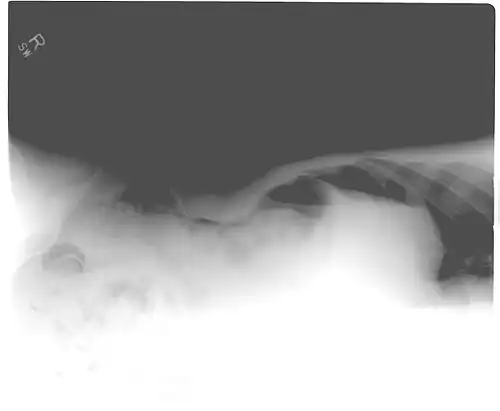

Another pneumoperitoneum on chest X-ray. -

Pneumoperitoneum seen on X-ray with the patient lying on his left side. -